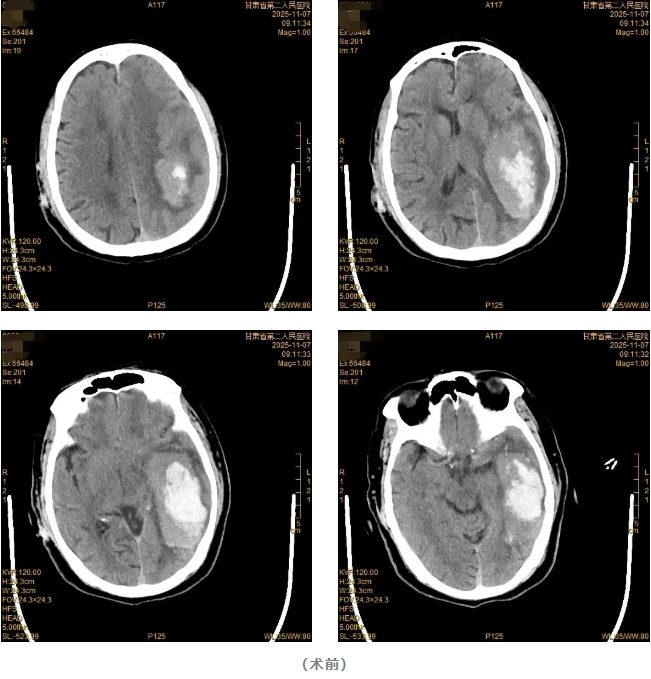

该患者因“突发意识不清伴右侧肢体无力9小时”由120急救车送至成人导航 。急诊查头颅CT显示:左侧颞顶叶脑出血,出血量约70ml。神经疾病中心团队迅速完善术前准备后,急诊为患者施行开颅血肿清除手术。手术过程顺利,术后患者意识逐渐恢复清醒,复查头颅CT确认颅内血肿已清除。